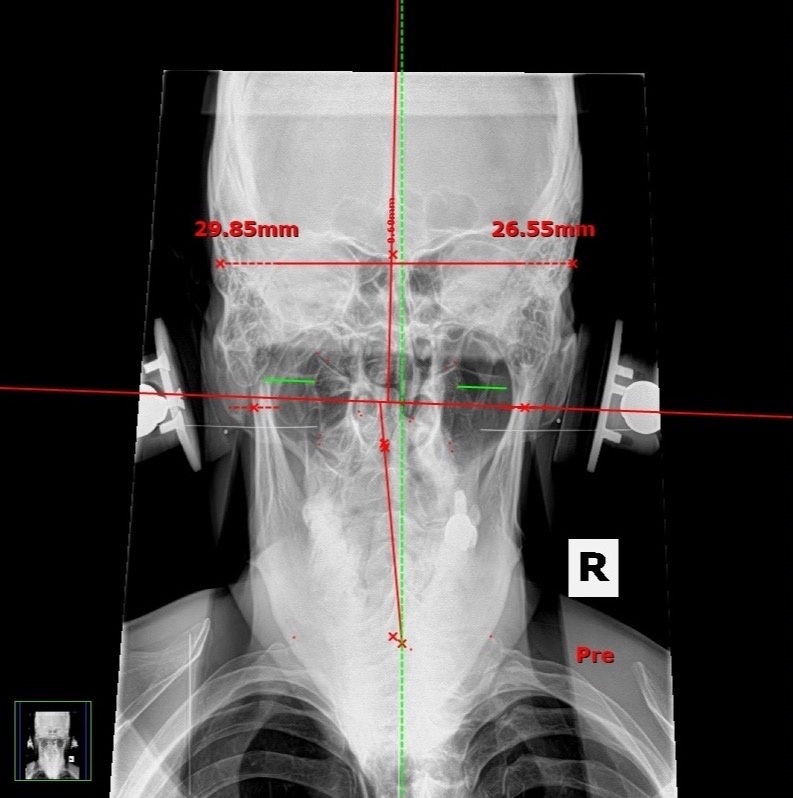

NUCCA Chiropractic Treatments to Fight Brain Inflammation

NUCCA to Lower Brain Inflammation

Dr Devin Young

When our head is out of alignment this can disrupt CSF flow and can affect our glymphatic system causing brain inflammation.

- Free NUCCA Assessment if you are in San Diego from Dr Devin Young